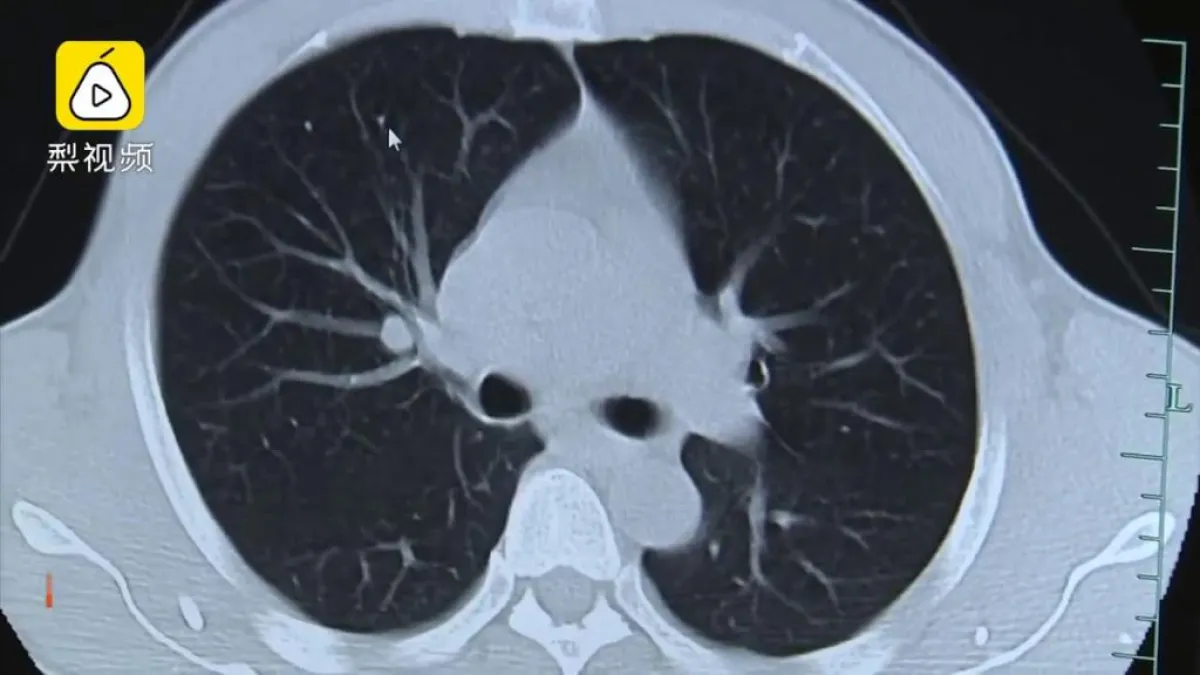

وقالت تقارير الإعلام الصينية أن الديدان ظهرت بوضوح في الصور التي تم إجراؤها لدماغ الرجل عبر تقنية المسح الضوئي. ولجأ المريض إلى إجراء تلك الصور لأن الأطباء المحليين حيث يسكن لم يتمكنوا من إدراك سبب الصداع.

وتم الإبقاء على جونغ-فا في غرفة العناية الفائقة لأيام واكتشف الأطباء انتشار ديدان أخرى في الجزء العلوي من جسمه، مثل الرئتين والعضلات داخل القفص الصدري.